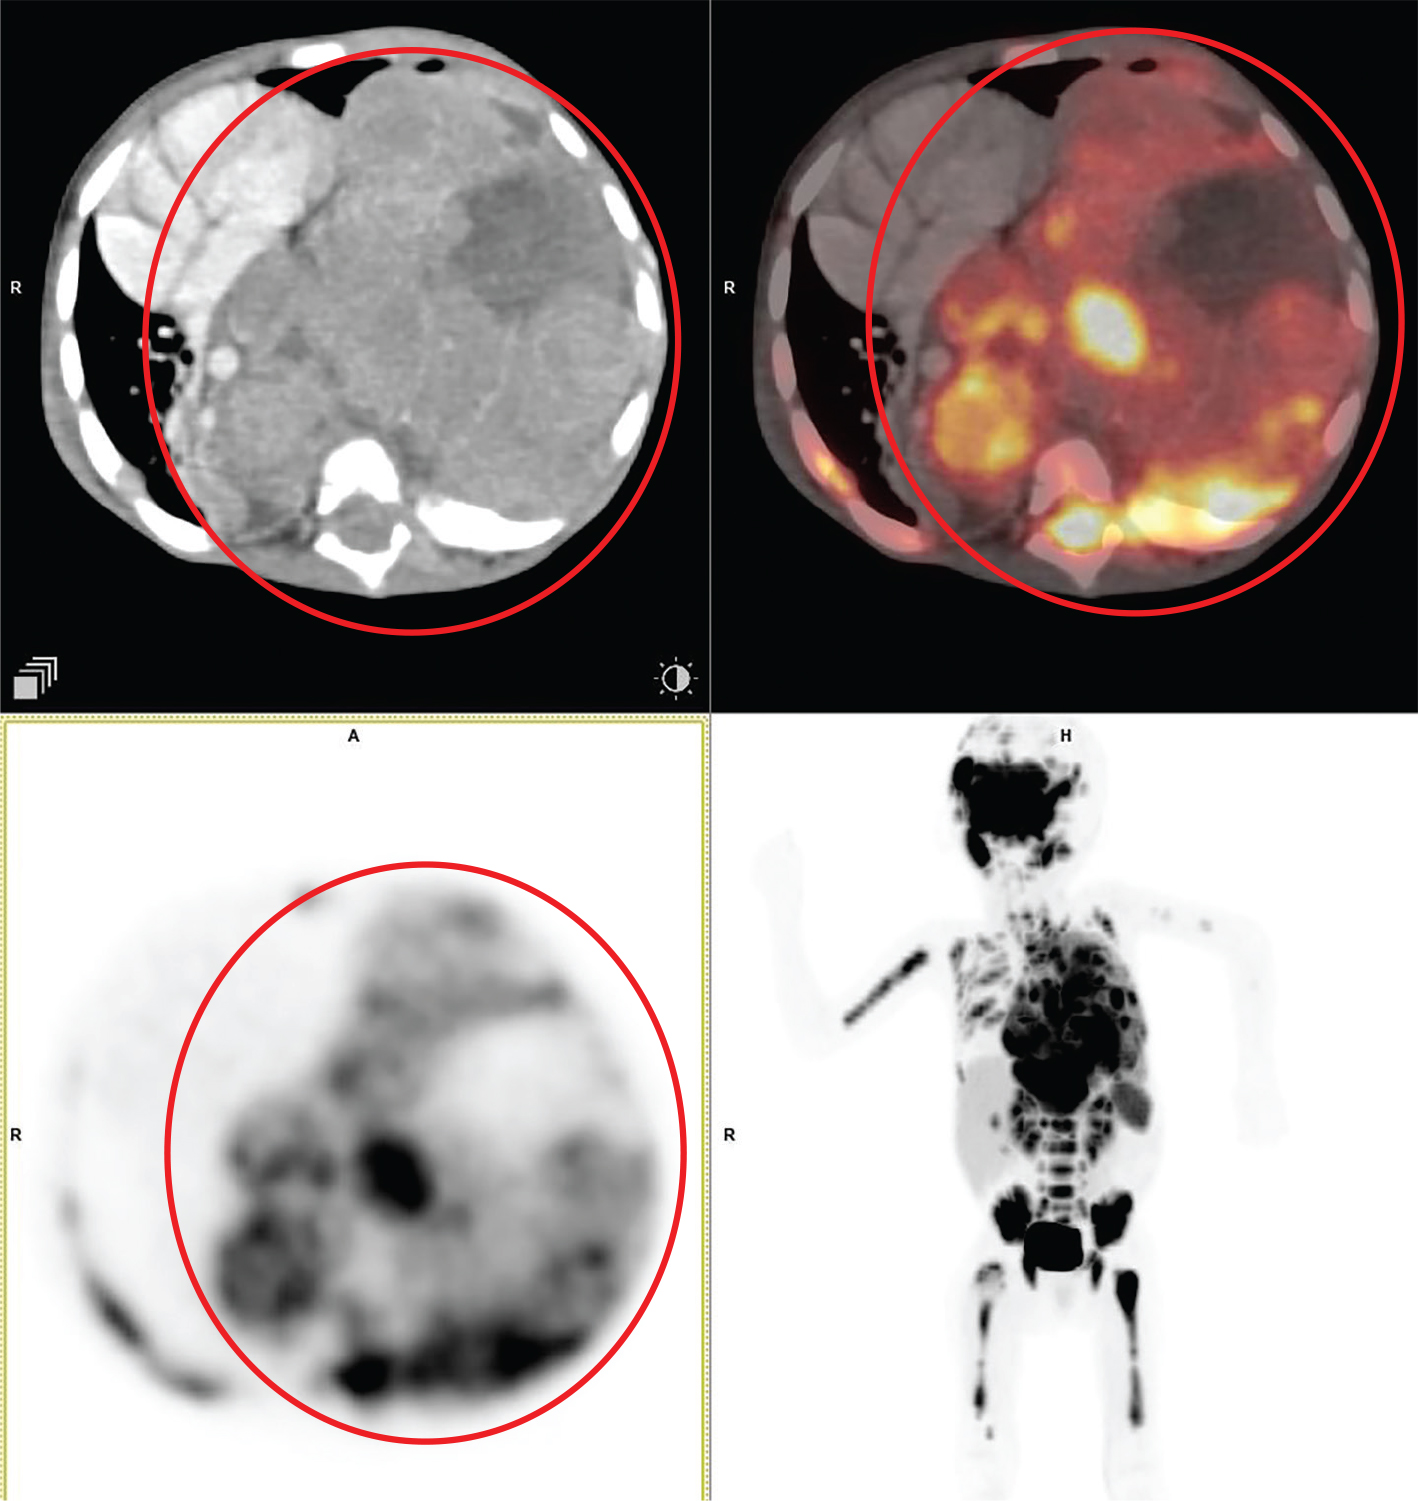

Fig 1

Figure 1. Type A thymoma. Anterior mediastinal mass that was pathologically confirmed as type A thymoma. FDG PET/CT images include axial CT (top left panel), fused axial PET/CT (top right panel), axial PET (bottom left panel), and maximum intensity projection (MIP) PET image (bottom right panel). In the red circle, there is a soft tissue density mass with well-defined contour showing homogenous enhancement in CT with moderate FDG uptake on PET. No evidence of infiltration of adjacent structures. No other metabolically active disease in the whole-body survey.